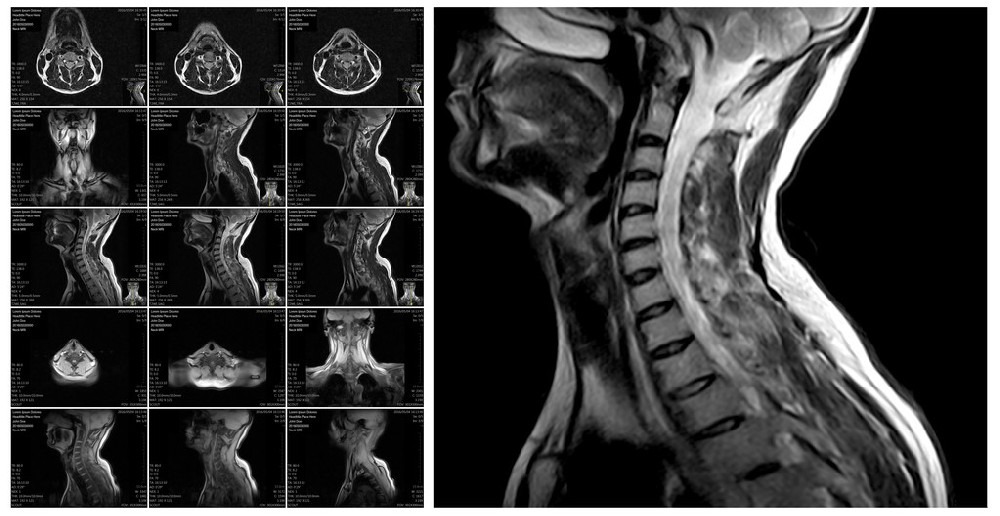

114例颈椎定点复位法加扶阳罐治疗颈椎小关节微错缝的临床观察

湖北省体育康复医院114例颈椎定点复位法加扶阳罐治疗颈椎小关节微错缝的临床观察--刊登在《湖北体育科技》 【作者】孙大桥;冯高基;王德燕; 【Author】 SUN Daqiao;FE...

中医扶阳罐干预神经根型颈椎病的效果评价

【作者】 高丛珊; 赵志新; 【Author】 GAO Congshan;ZHAO Zhixin;Shanxi University of Chinese Medicine; 【通讯作者】 赵志新; 【机构】 山西中医药大学; 山西省中医院; 【摘要】 [目的]探讨扶阳罐...